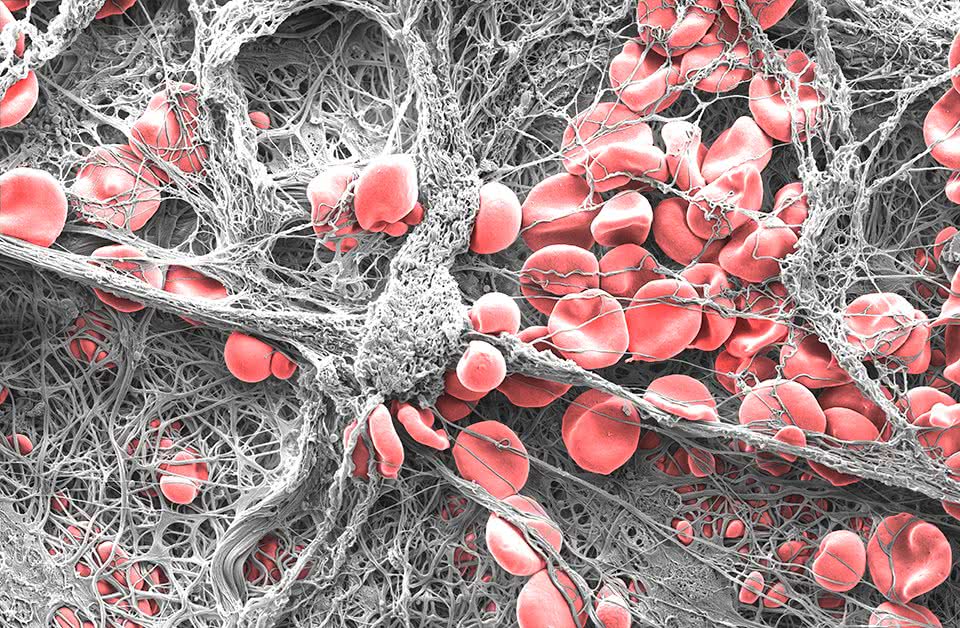

Clotted

Eli Moore

Centre for Cancer Biology